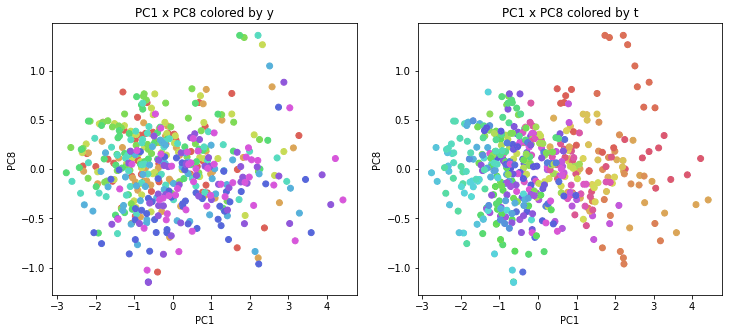

PCAの結果の第n主成分をPCnと表記します。

医療費データの場合と同様に、PCAの結果を見やすく表示するため、seabornのカラーパレットを使って、年月別、都道府県別に色分けして図示してみます(左側が年月別に色分け、右側が都道府県別に色分け)。PC1~PC8まで表示しました。

医療費データの場合ほどはっきりとはしていませんが、PC2が概ね時間の経過を表す成分で、残りの成分が時点によって変わらない地域の特徴を表す成分となっているようです。

また、PC1×PC3を見ると、47沖縄が他の都道府県からかなり離れたところに位置しており、沖縄の地域差が際立っているのが分かります。これは、以前別の記事で年齢階級のない健診データでPCAを実行した場合と似た結果となっています。

今回は、医療費データと同様に、健診データ240次元についてPCAを実行してみました。PCAの結果、医療費データの場合ほどはっきりしとはしていませんが、第2主成分が概ね時間の経過を表す成分で、時間軸に沿った全体的な動き(全国的な動き)を表しており、それ以外の成分が地域の特徴を表す成分で、この10年間あまり変わっていないことがわかりました。